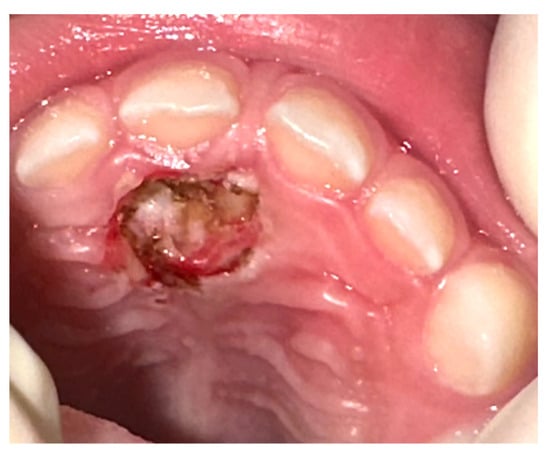

2. Case Presentation

| 19 | This study (2023) | Male/4 years | Maxilla, palatal region | Peripheral ossifying fibroma | Peripheral developing odontoma | Surgical laser excision |